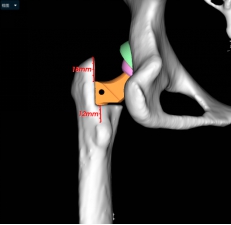

小张入院后,立即开始逐步进行相关检查,进行术前的准备。因为DDH的手术一般比较复杂,特别是这种脱位程度较高的患者,所以术前就需要更加精准的规划。对于小张的手术方法,耿硕制定了两套方案:一是如果原来真臼内及股骨头的软骨条件良好并且相匹配的话,那么可以尝试将股骨头放进髋臼里配合骨盆截骨重建髋关节;二是如果软骨条件不好或难以匹配,那么只能行全髋关节置换术。但是所有手术方案都会有一个挑战,就是如果在安装完髋臼杯及股骨假体后复位时把股骨下拉过多,可能会造成神经等软组织的牵拉伤并且因软组织张力过大可能造成假体松动,为了避免这种情况可能需要行股骨截骨减张,这样一期便不能恢复双下肢等长,需二期行骨延长术恢复下肢等长。在术前,为了适应软组织的张力状态及验证复位可能性,小张入院后即进行了患肢的牵引处置。为了精准的对手术做出规划,术前小张进行了下肢全长的三维CT扫描和模型重建,并且应用人工智能系统AI HIP对其进行术前手术方案的制定。人工智能能够利用患者的三维CT数据进行智能化识别解剖位点,匹配假体的大小及安放位置,通过对手术精准地预演,让外科医生在术前心中有数。通过人工智能系统的规划,计算出小张同学的双下肢腿长差和偏距差,计算出了旋转中心所需下移的距离和假体需要安放的位置等,髋关节置换方案为S-ROM假体系统,髋臼杯为PINNACLE 44号,内衬为BIOLOX28-44,因为患者比较年轻,所以选用了陶瓷对陶瓷的摩擦界面,能够实现更长的使用年限。根据术前规划数据,毕郑刚、耿硕团队提前准备了相应的假体和器械,为手术做了充分的准备。

(人工智能精准术前规划)